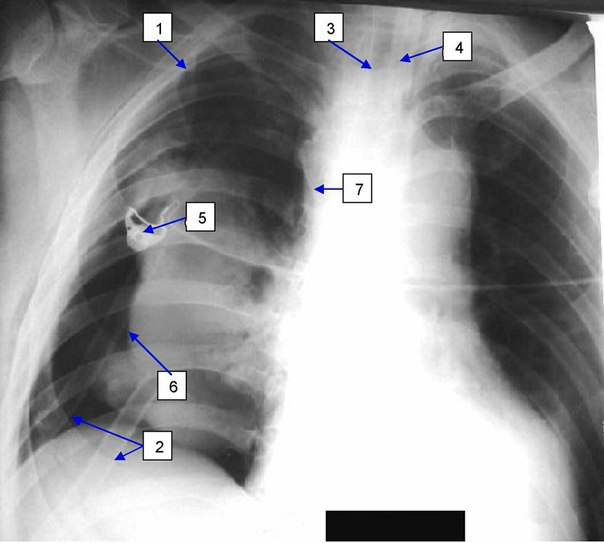

Пневмоторакс как осложнение катетеризации центральных вен